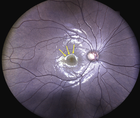

Fundus photography remains the gold standard for diagnosing and staging nonexudative AMD. In 2013, the Beckman Initiative for Macular Research published a classification system to assist eye care providers in identifying AMD-related structural changes (see AMD Classification).10

OCT is also valuable in identifying AMD at early stages. Drusen, a hallmark of AMD, are identified on OCT as discrete elevations of the retinal pigment epithelium (RPE) layer at the level of Bruch membrane (Figure). Drusen that form above the RPE are known as reticular pseudodrusen and are a more ominous sign. Patients with this type of drusen are much more likely to progress to advanced disease.11